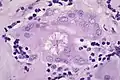

Micrograph of asteroid bodies in pulmonary sarcoidosis. H&E stain. Asteroid body in sarcoidosis.

Asteroid body in sarcoidosis.